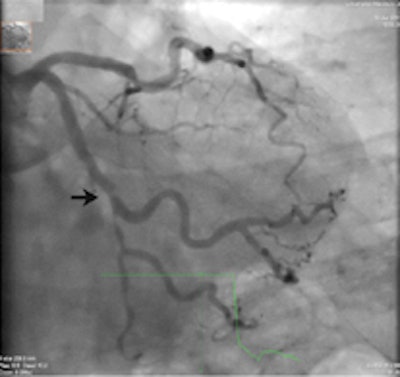

A 64-year-old patient with carotid stenosis. Top left: Coronary CT angiography image. White arrow points to a soft plaque in the midcircumflex artery, with stenosis of the lumen. Calcium score was 64. Top right: Short-axis image of the adenosine perfusion MRI examination. White arrow points to a perfusion defect in the posterolateral wall, during stress. The perfusion defect was not present in the rest series, thus indicating inducible ischemia. Bottom left: Invasive coronary angiography image of the left coronary arteries. Black arrow points to a significant stenosis, corresponding with the location seen on CT. Bottom right: Invasive coronary angiography image after intervention. Good results were achieved after percutaneous coronary intervention with stent placement. All images courtesy of Drs. Rozemarijn Vliegenthart and Martijn den Dekker.Two centers in the Netherlands scanned 115 cardiac-asymptomatic patients age 50 years and older (mean age 65 years; 76% men) with proven aneurismal or stenotic arterial disease with CT, MRI, and sometimes echocardiography as well.